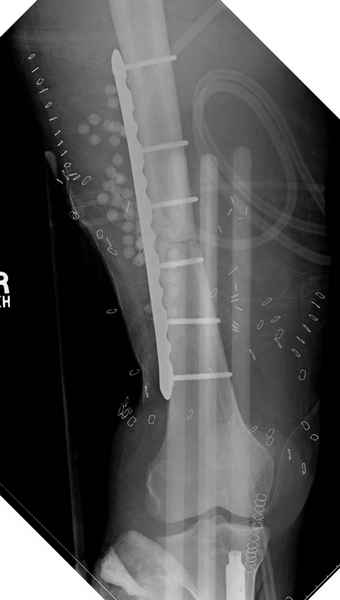

Больному с политравмой установлен наружный "spanning-bridging" фиксатор, после нескольких Irrigation&Debridment на фоне отрицательного посева из раны, через открытый участок установлен 4.5 mm Locking Plate.

На фоне фиксированного перелома бедра мероприятия по восстановлению мягкотканого покрова. Перелом голени зафиксирован после стабилизации бедра традиционным методом.